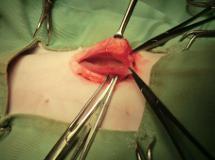

尿管切開による結石摘出

尿管移設